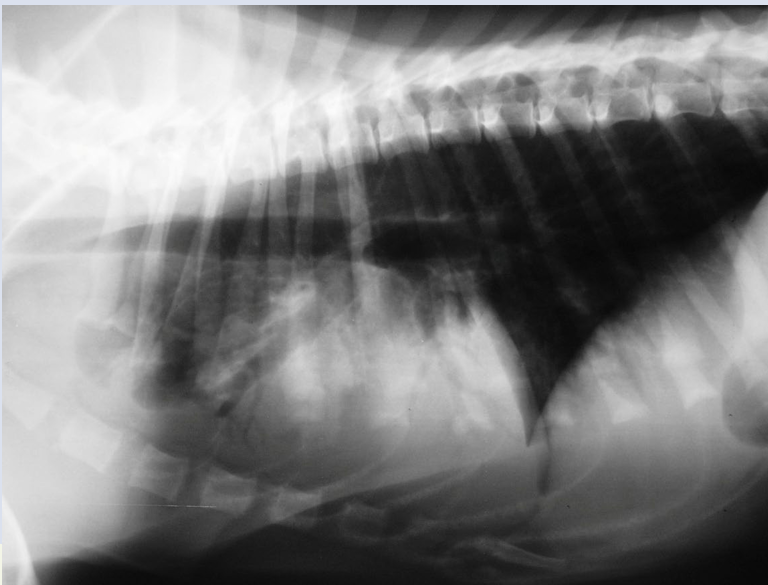

Bronchial pattern

have donut or ring

Atelectasis (Alveolar pattern)

collapsed lung